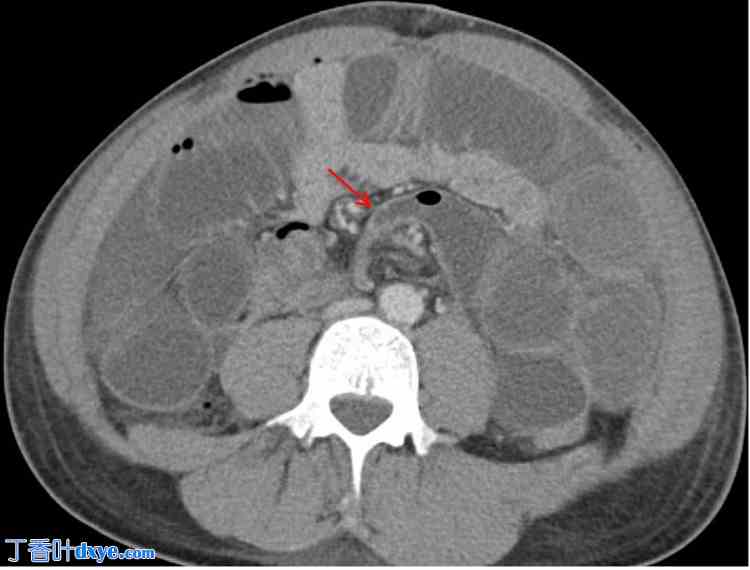

术后第二天,患者出现恶心、呕吐和腹胀。CT 扫描显示腹部中央、肠系膜内、手术吻合口近端存在小肠闭环梗阻(图 2、3)。这提示可能存在内疝或其他术后并发症。

图 3. 腹部及盆腔增强 CT(轴向位)显示小肠闭式梗阻(红色箭头),位于腹部中部肠系膜,靠近手术吻合口。